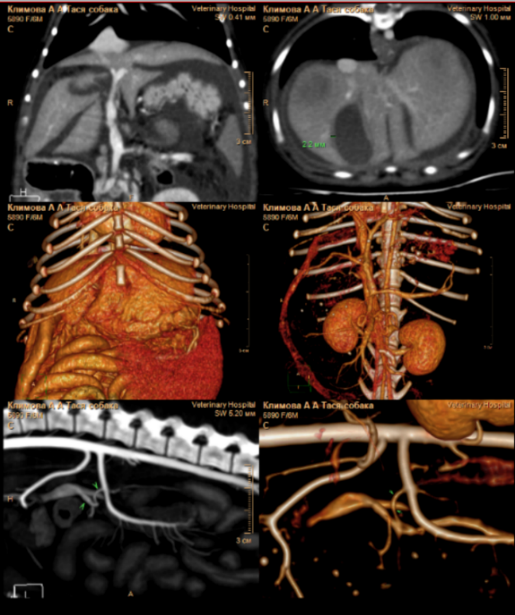

По результатам КТ-ангиографии выявлены следующие изменения (фото 2):

• множественные портокавальные анастомозы, предположительно, приобретенного характера;

• микрогепатия и отек стенки желчного пузыря;

• отек паренхимы поджелудочной железы;

• изменения в стенках желудка и тонкого кишечника, вероятно, обусловленные венозным застоем или воспалительными процессами;

• наличие асцита.

На основании результатов КТ-ангиографии диагноз «врожденный портосистемный шунт» не подтвердился. Были выявлены признаки портальной гипертензии, предположительно, обусловленные первичной патологией печени. Это привело к развитию приобретенных портосистемных шунтов, к отеку паренхимы поджелудочной железы, стенок желчного пузыря и кишечника, а также к асциту вследствие венозного застоя в брюшной полости.